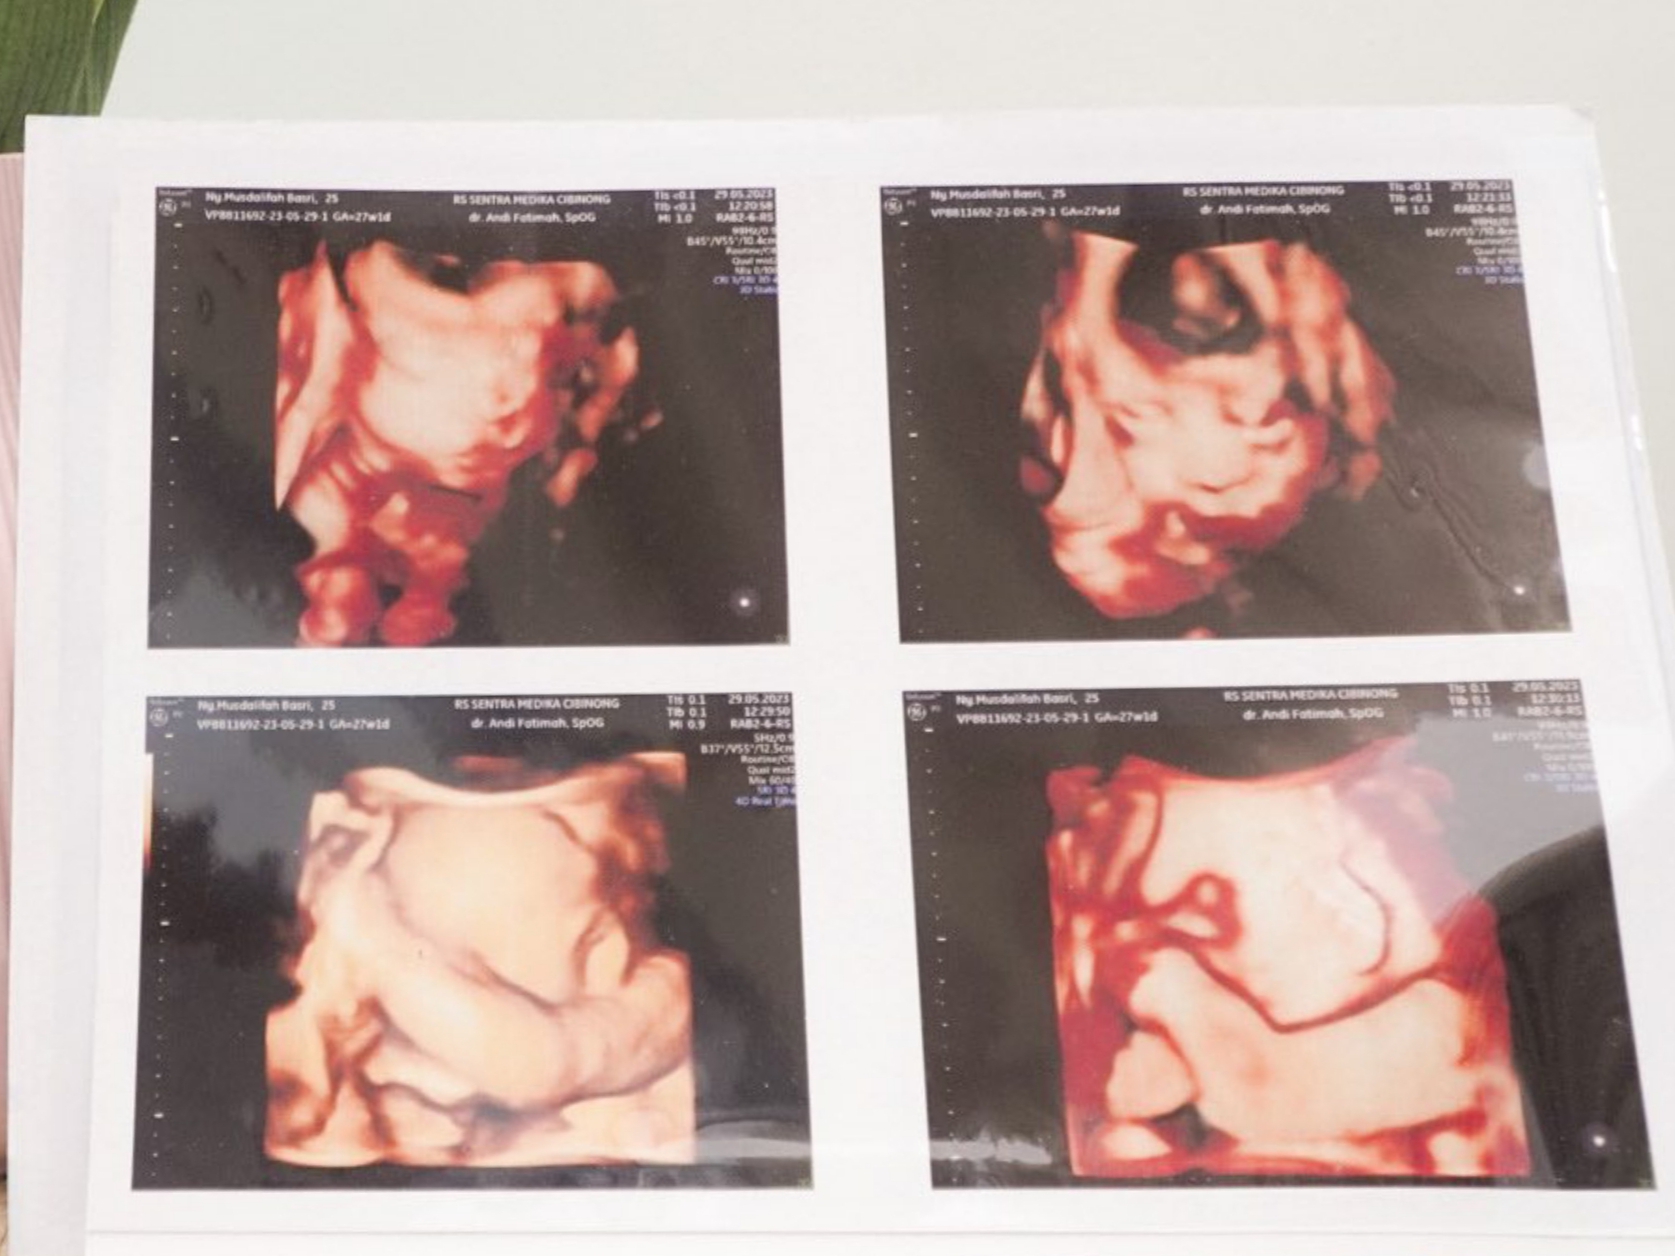

Benar saja, pada awal 2023, Musdalifah dan suami lewat akun Instagram menunjukkan hasil USG dan test pack. Pada postingan tersebut, terlihat dengan jelas gambar kantung kehamilan yang berjumlah dua dengan tulisan “twin pregnant” pada kertas pemeriksaan kehamilan. Selain itu, Musdalifah juga menulis caption, “Alhamdulillah tahun 2023 diawali dengan kebahagiaan. Doain ya guys.”